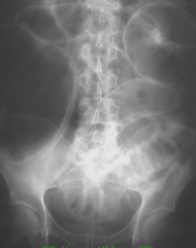

A patient presents with crampy abdominal pain associated with bilious vomiting, abdominal distension and constipation. They have had previous abdominal surgery

SBO

Causes: adhesions from previous surgery, inguinal hernia with incarceration, Crohn’s disease, malignancy, appendicitis